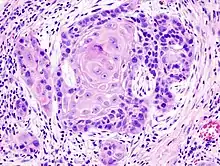

Biopsy of a highly differentiated squamous-cell carcinoma of the mouth. Typical squamous-cell carcinoma cells are large with abundant eosinophilic cytoplasm and large, often vesicular, nuclei.[11] Haematoxylin & eosin stain